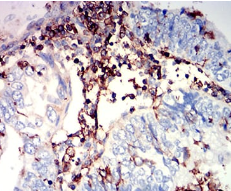

IHC    1/200 - 1/1000